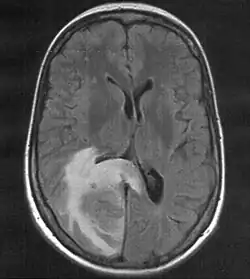

MRT mit T2-Flair-Wichtung, die zugehörige PET-Untersuchung ist weiter unten abgebildet.

Kernspintomographie

Die Kernspintomographie weist bei besserer Weichteildifferenzierung, insbesondere nach Gabe von Gadolinium als Kontrastmittel, eine deutlich höhere Sensitivität auf und ist somit geeigneter für die Suche nach Hirnmetastasen. So ist im Vergleich zur CT-Untersuchung die Rate der Patienten mit im MRT nachgewiesenen Hirnmetastasen mehr als doppelt so hoch.[8] Das gilt besonders für sehr kleine Befunde und Metastasen im Bereich der hinteren Schädelgrube. Die Kernspintomographie kann zur Abgrenzung gegen Hirnabszesse oder andere möglicherweise ähnlich imponierende Läsionen um eine Kernspinresonanzspektroskopie ergänzt werden.[9]